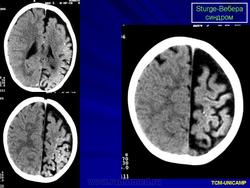

Рентгенологически можно обнаружить обызвествление в затылочных и теменных отделах мозга. При ПЭГ у большинства больных отмечаются атрофия вещества мозга, расширение субарахноидальных щелей на конвекситальной поверхности и расширение полостей желудочков мозга.

Диагноз синдрома Стерджа - Вебера не представляет трудностей. Наличие корковых обызвествлений можно выявить при рентгенографии. Характерные тени располагаются в виде двойных контуров, повторяющих извилины пораженных долей мозга. Компьютерная томография выявляет более обширные области обызвествления, чем это видно при обычной рентгенографии.

Компьютерная томография пациента с болезнью Штурге - Вебера